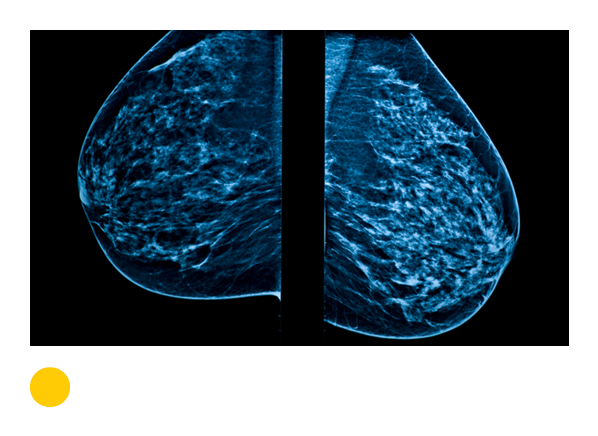

Mammogram

Uses low-dose X-rays to spot masses and mineral deposits that could indicate breast cancer. Radiation exposure: low.

0.4

7 weeks

Needed every two years for women ages 50 to 74.